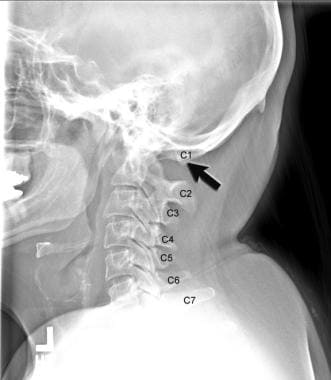

Рентген шейных позвонков при спина бифида

Раздел: Фотозарисовки